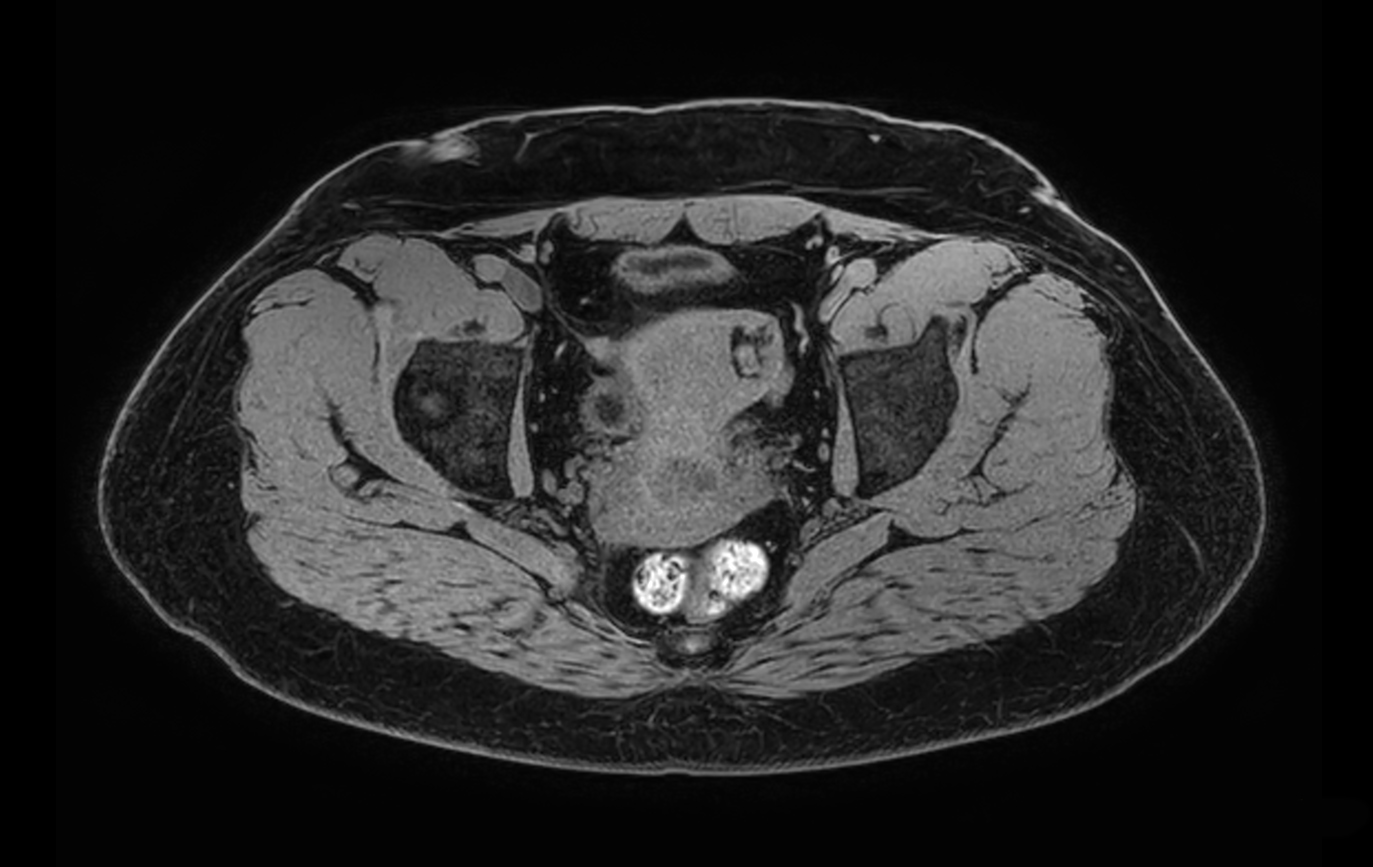

Axial T1w SPIR